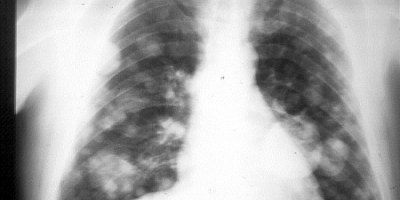

CORONAVIRUS, IMSS, Información Nacional

CORONAVIRUS, Información Internacional

CORONAVIRUS, Información de los Estados